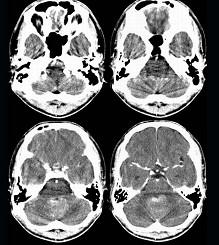

问题 男,16岁,头痛、呕吐10天,CT检查如图所示,最可能的诊断为()

选项 A.脑膜瘤 B.髓母细胞瘤 C.室管膜瘤 D.脑血管瘤 E.血管母细胞瘤

答案 B